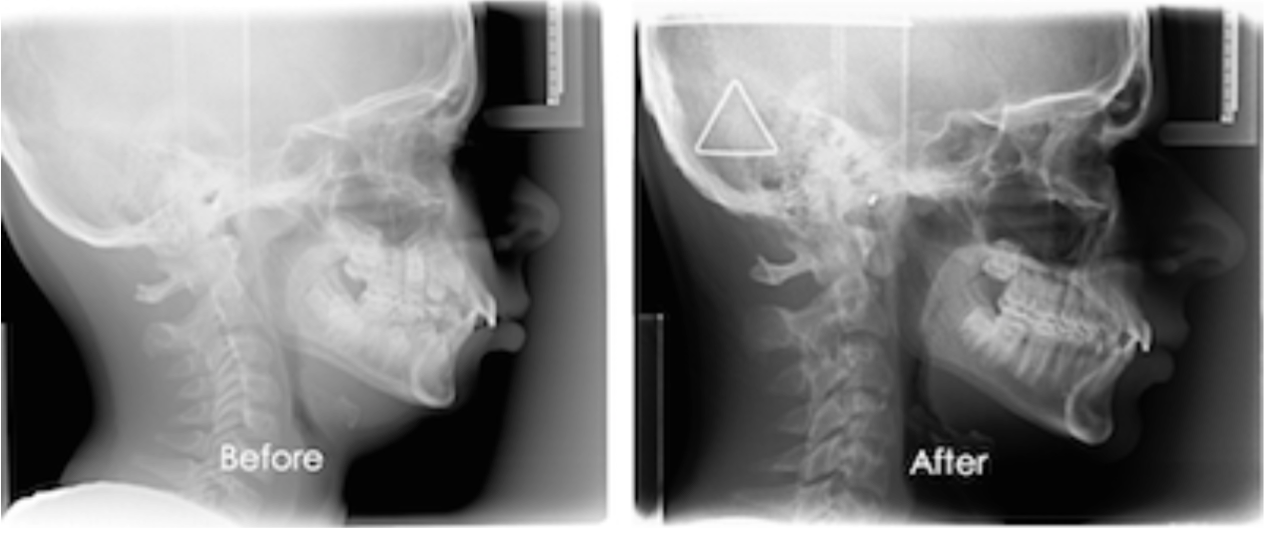

HealthyStart™️ corrects the tongue position and breathing habits while passively treating malocclusions to effect the appearance of the child’s face and smile.  Treating early allows the HealthyStart™️ treatment to permanently correct these conditions rather than the band-aid remedies millions of adults are left with as their only recourse.

Children can accomplish most of this at night while sleeping by wearing the soft mouth appliance to correct their tongue position and stop snoring, stop mouth breathing, stop bed-wetting, stop restricting their airway and stop many of the symptoms that can confuse even the most experienced professionals in the appearance of ADD/ADHD.  The appliance guides the jaw and arches to its’ intended size and position so that the teeth erupt in place for a beautiful and healthy smile.  This permanent solution prevents relapse when started in the younger growth years of the child’s life.